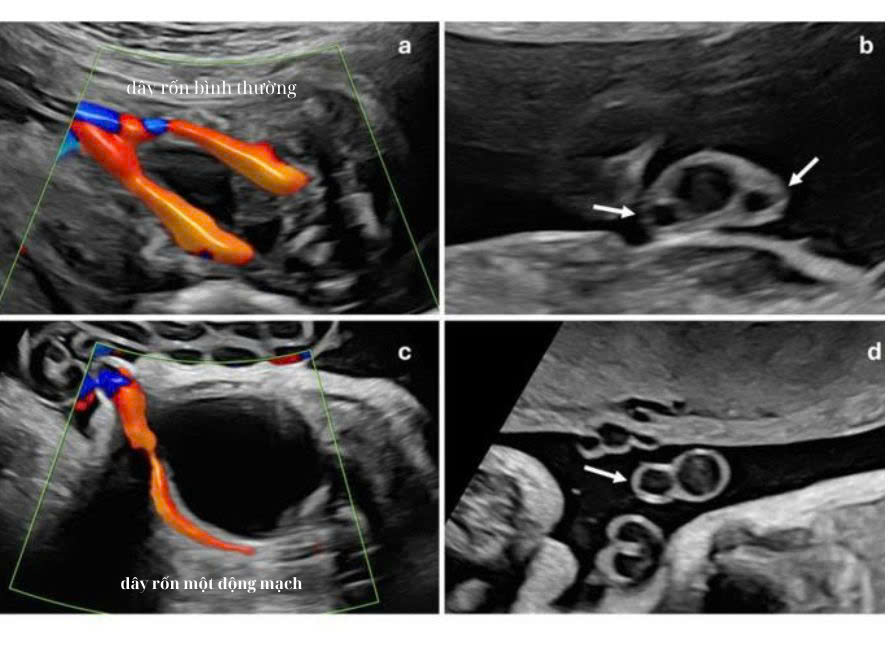

Cần hiểu đúng về cấu trúc dây rốn bình thường. Dây rốn thường có ba mạch máu. Gồm hai động mạch và một tĩnh mạch. Khi chỉ còn một động mạch, tình trạng này gọi là dây rốn một động mạch.

Dây rốn một động mạch thường được phát hiện khi siêu âm hình thái giữa thai kỳ. Ở giai đoạn này, mạch máu đủ lớn để quan sát rõ số lượng. Bác sĩ sẽ nhìn mặt cắt ngang dây rốn để đếm số mạch. Đồng thời kiểm tra mạch máu chạy hai bên bàng quang thai.

Nếu chỉ thấy mạch ở một bên bàng quang, đây là dấu hiệu đặc trưng của tình trạng chỉ còn một động mạch rốn. Cách kiểm tra này giúp tăng độ chính xác. Trong một số trường hợp, dây rốn xoắn nhiều hoặc hai động mạch dính đoạn ngắn gần bánh nhau có thể gây nhầm lẫn. Vì vậy, siêu âm kiểm tra lại là bước cần thiết trước khi kết luận.